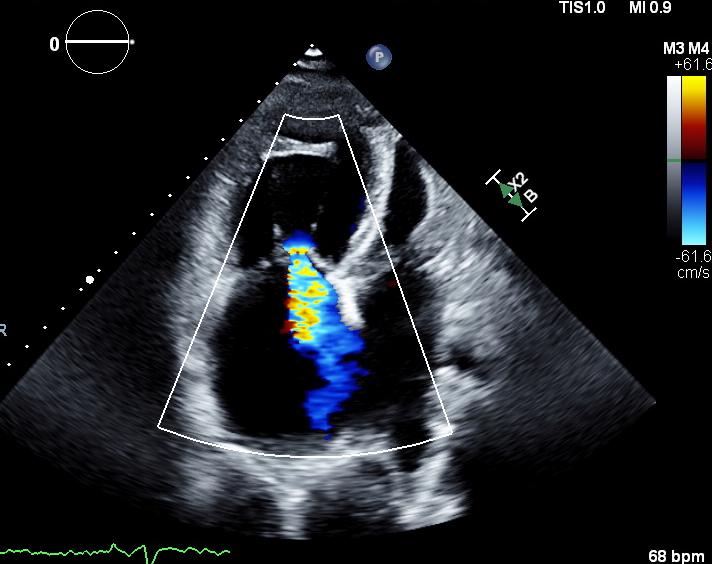

EF 56% (Simpsons),

Secundum ASD with bidirectional shunt

Dilated RA and RV